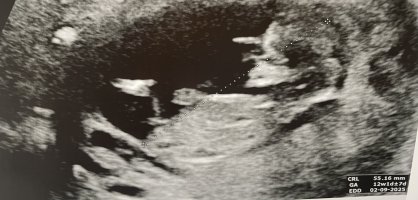

Tässä en näe itse mitään. Tosiaan 12+1 osa on jo poikamaisia, mutta tyttölupaukset muuttuu vielä herkästi myös pojiksi.Hei viisaammat, kun tää tyyppi on tollee istuma-asennossa melkein, niin mikä tossa nyt sit vois olla kulma?Ultran mukaan raskaus 12+1, eli onko kaikki vielä tytön näkösiä tässäkohtaa?

Hei apua aivan, toihan on jalan luu?Tässä en näe itse mitään. Tosiaan 12+1 osa on jo poikamaisia, mutta tyttölupaukset muuttuu vielä herkästi myös pojiksi.

No nyt on minullekin liika hankala!Hei apua aivan, toihan on jalan luu?

Tässä kuvassa molemmat jalat+ nub vai onko? Kiitos joka tapauksessa kommentista, oisin ennustellu ilosesti tosta jalasta menemään![]()

Kasvaako meiän lapsella kolme jalkaa?No nyt on minullekin liika hankala!Mä sanoisin ettei ole nub sijainnin perusteella.